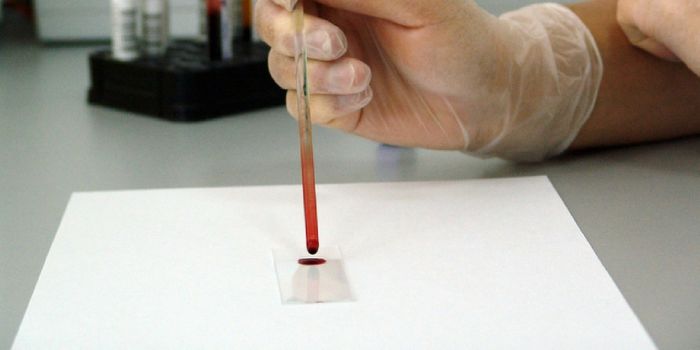

JAN 19, 2025Clinical & Molecular DXWhen cancer is detected earlier, it can improve outcomes for patients. Liquid biopsies are one way to improve cancer det ...

AUG 22, 2023Clinical & Molecular DXWith just a blood sample, clinicians may soon be able to quickly diagnose the cause of illness in children. The test can ...

MAR 24, 2020Clinical & Molecular DXResearchers from the Broad and Dana-Farber Cancer Institutes have developed a diagnostic technology that can moni ...

MAR 23, 2020Genetics & GenomicsLiquid biopsies aim to diagnose a disease with only a bit of biological fluid, usually blood.